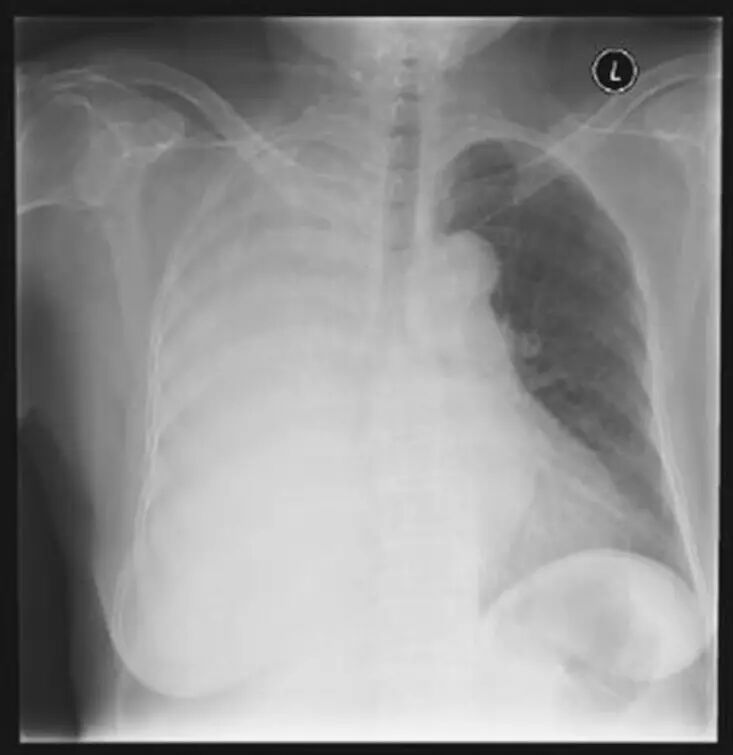

胸部影像学检查可提供关于胸腔积液性质的重要信息,包括位置、大小和积液的流动性。后前位(PA)胸片是首选的胸部成像技术,少量积液(前后位片约200mL,侧位片约50mL)即可通过肋膈角变钝来识别。而如前所述,大量胸腔积液最常见于恶性肿瘤。胸部平片也可为积液的病因提供线索,如支气管腔内阻塞性病变(图65-1)。

图65-1 大量胸腔积液患者的前后位胸片,可见支气管腔内阻塞性病变导致右主支气管截断征而纵隔仍居中。